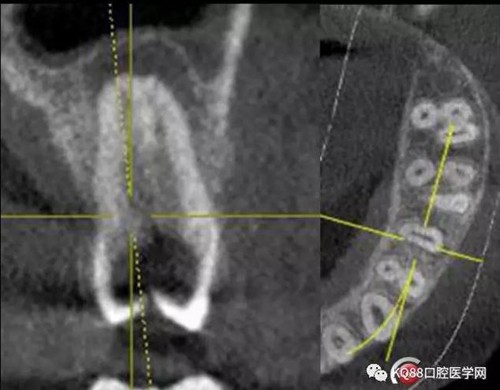

25遠(yuǎn)中鄰牙合面齲壞達(dá)髓腔,引起的牙髓炎,之后發(fā)展成為根尖炎的一個(gè)常見(jiàn)病例,上頜前磨牙,一看,心理都會(huì)覺(jué)得有啥啊,兩個(gè)根管,開(kāi)髓后,直接擴(kuò)了,不會(huì)有任何壓力,幸運(yùn)的是我們有CT,所以我就開(kāi)始都會(huì)定位下根管口,然后看到的事情告訴我其實(shí)上頜前磨牙不一定有我們想象的那么簡(jiǎn)單。

這兩張角度的截圖告訴我們這個(gè)牙齒一個(gè)典型的Y型根管,髓腔非常巨大,從根管口看,貌似一個(gè)根管口,但是根管銼下去以后,會(huì)兩個(gè)方向角度的分開(kāi)。因?yàn)槲覀儸F(xiàn)在都是常規(guī)的機(jī)擴(kuò)與熱牙膠充填,建立直線根管口的暴露就變得非常重要,必須直線視野下操作,機(jī)擴(kuò)才不會(huì)發(fā)生扭曲折斷。目前市面上的根管銼有很多,M3,S3等,而此次我使用的是歐羅德卡PLEX軟銼,因?yàn)槭强谇?8贈(zèng)送我的,所以我就先嘗試的使用了一下,我不會(huì)單方面的去評(píng)價(jià)比別的好,我覺(jué)得預(yù)備方法對(duì)了,都會(huì)很不錯(cuò),只能說(shuō)一句這個(gè)用起來(lái)軟銼對(duì)后牙的預(yù)備確實(shí)不錯(cuò)。根管預(yù)備,常規(guī)我都會(huì)先C銼疏通,如果直接15號(hào)很有可能會(huì)在根尖方形成臺(tái)階,以后就很難再下去了,當(dāng)C銼到達(dá)根尖孔后,予以初步測(cè)量長(zhǎng)度,在用疏通機(jī)擴(kuò)針通入,然后一步步規(guī)范化開(kāi)始,逐級(jí)預(yù)備,一個(gè)簡(jiǎn)單的經(jīng)驗(yàn),如果當(dāng)使用的銼不容易到達(dá)根尖時(shí),不要著急,用上一號(hào),繼續(xù),再回來(lái),就可以了,不然形成臺(tái)階,就很難操作了,常有人會(huì)覺(jué)得擴(kuò)根時(shí),突然發(fā)現(xiàn),下不去了,排除斷針的可能性的話,臺(tái)階是最重要的,擴(kuò)根時(shí),1%次氯酸鈉變沖洗,變預(yù)備,防止碎屑推出根尖孔,我沖洗常使用1%次氯酸鈉與蒸餾水,再充填前,會(huì)使用EDTA沖洗液去除根管壁油污。